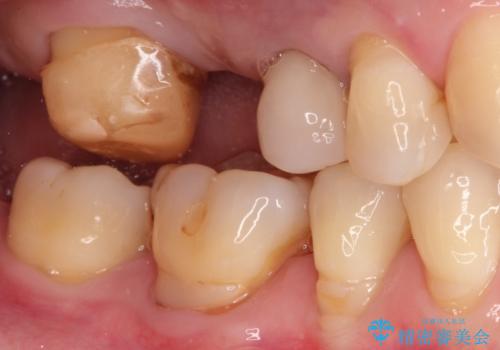

奥歯のオールセラミックブリッジ

- 矯正後に欠損補綴を主訴に来院されました。

オールセラミッククラウンのブリッジ修復にて治療を行っております。

抜歯してから歯周組織が安定するまで期間がかかります。

十分に期間を治癒を待つことで審美性や清掃性の高い被せものを製作できます。